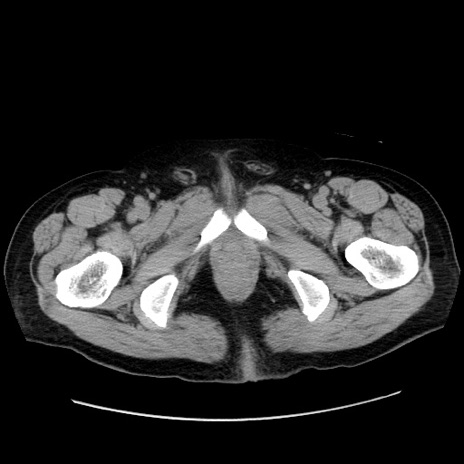

症例30(横断像)

【症例】80歳代男性

【主訴】臍周囲痛

【現病歴】約6時間前から臍下部痛が出現。次第に腹部膨隆・背部痛も生じてきたため来院。背部痛の場所は変化しない。

【既往歴】腎盂腎炎

【身体所見】意識清明、BT 36.3℃、BP  131/87mmHg、P 87bpm、SpO2 100%(RA)、臍周囲自発痛・圧痛あり、反跳痛なし、自発痛部位に一致して板状硬あり、腹部膨隆、腸雑音減弱、CVA tenderness両側陰性。

【データ】WBC 19600、CRP 0.33